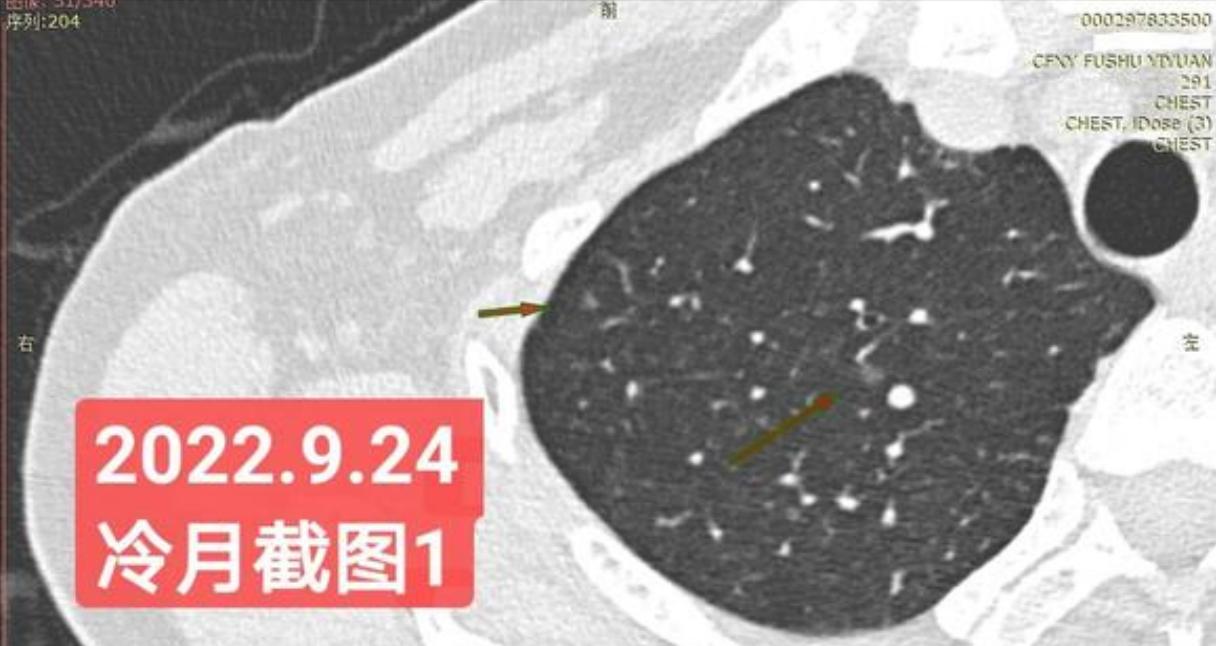

非常感谢戴主任和冷月等几位吧主的无私奉献,你们牺牲自己的休息时间,为广大患者排忧解难,你们对待病人,如同亲人一样,真的好感动!上次,在贴吧里咨询过戴主任关于我的肺结节情况,戴主任说,我右肺下叶那个结节高危。心里好害怕,距离上次CT间隔三个月,我又做了肺部CT,这次还要劳烦戴主任以及吧主们,帮我看看我的肺结节,严重吗?需要马上手术吗?

我昨天把我五次肺部CT电子版以及报告,发给了冷月吧主,昨天晚上,冷月吧主就为我截好图,发给我,非常令我感动,谢谢您冷月吧主,您辛苦了,您要多休息,不要太辛苦了。

我是21年7月做肺部CT,报告给报出0.5厘米肺结节。(但大夫说,20年就已经有那个肺结节了,因为小,报告没给报)。自发现肺结节后,吃了四个月中药,结节没有缩小,反而增大了。今年8月1日开始到现在,又吃了近两个月的蒙药了。 结节还是没有缩小,反而在增大。21年7月到现在,复查过3次肺部CT了。结节一直在增大。最近一次复查时间是2022年9月24日。

上次找戴主任贴吧咨询过,主任说我右肺下叶那个结节高危,距离上次CT,到现在三个月复查肺部CT。所以9月24日又复查做了肺部CT。

右下肺结节高危,肺窗已经到亚实性阶段CTR>0.5,纵膈窗可见实性,目前已经不属于异质混磨,而且PSN亚实性结节。